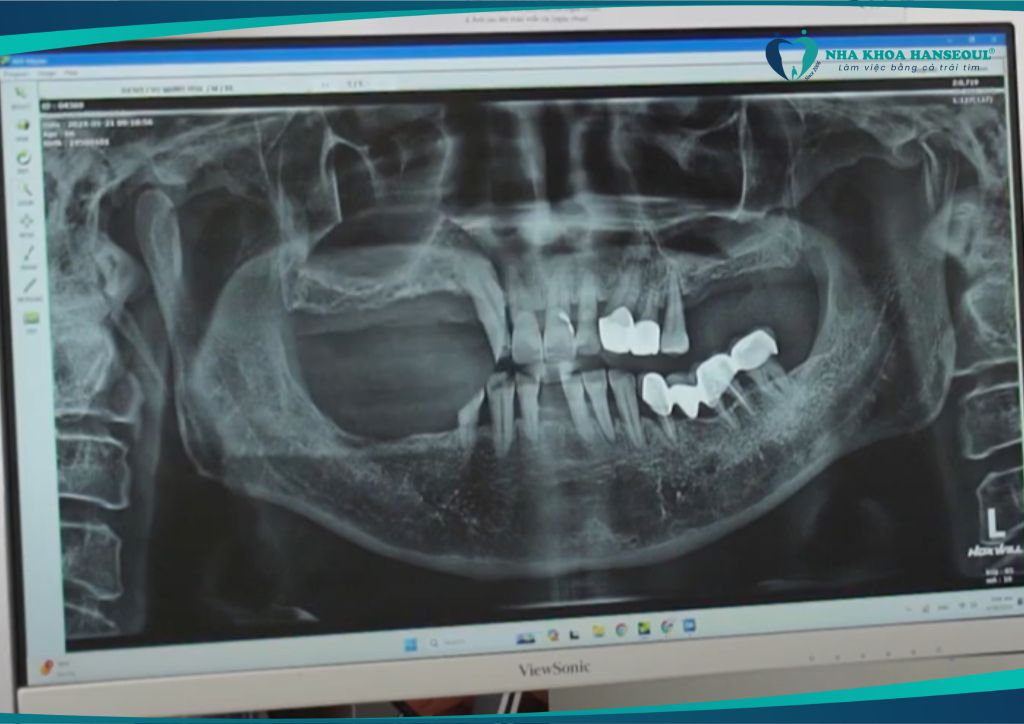

Chú Vũ Mạnh Hòa sinh năm 1958 (66 tuổi), đã sinh sống, làm việc tại Cộng hòa Séc nhiều năm. Do yếu tố tuổi tác và tình trạng răng miệng không được chăm sóc đúng cách, chú bị mất tới 14 răng, chủ yếu là các răng hàm chịu lực ăn nhai.

Sau khi được các bác sĩ thăm khám và chụp phim kỹ lưỡng, chú được chỉ định phục hình toàn diện bằng công nghệ cấy ghép răng Implant Hansafe. Đây là giải pháp hiện đại giúp phục hồi răng mất an toàn, không đau, ăn nhai như răng thật.